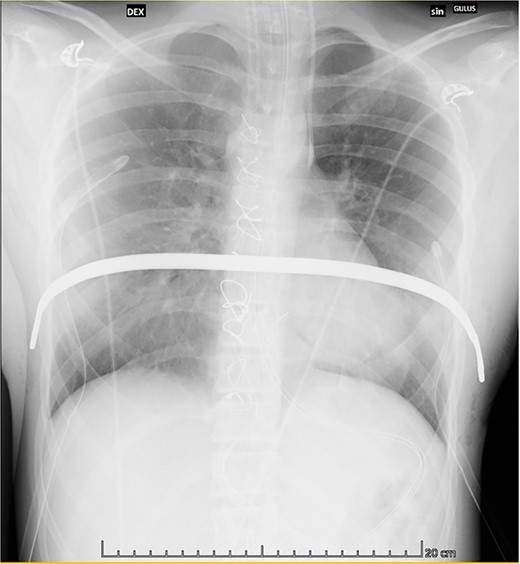

A 12-year-old female patient with severe PE was admitted for an elective MIRPE. Upon exertion, she complained of shortness of breath and feeling of pressure in the chest. Cosmetic concerns were expressed by the patient and her family. Inspection and palpation of the thoracic region revealed a deep conical depression of the chest wall. Preoperative electrocardiogram, echocardiography and pulmonary function tests at rest were normal. Computed tomography (CT) showed a Haller index 4.9, indicating cardiac displacement to the left and rotation of the sternum to the right by 35° (Fig. 1).

Preoperative computed tomography demonstrating severe pectus excavatum with Haller’s index 4.9.